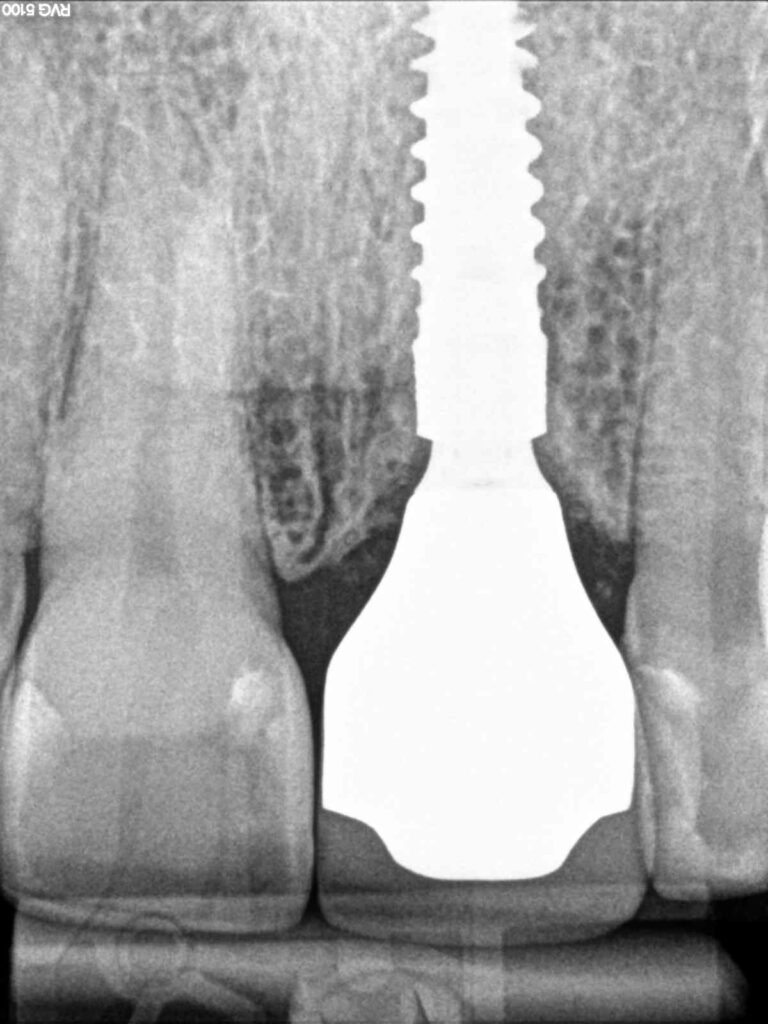

Fig. 7: Radiograph showing implant and implant-supported final crown 21